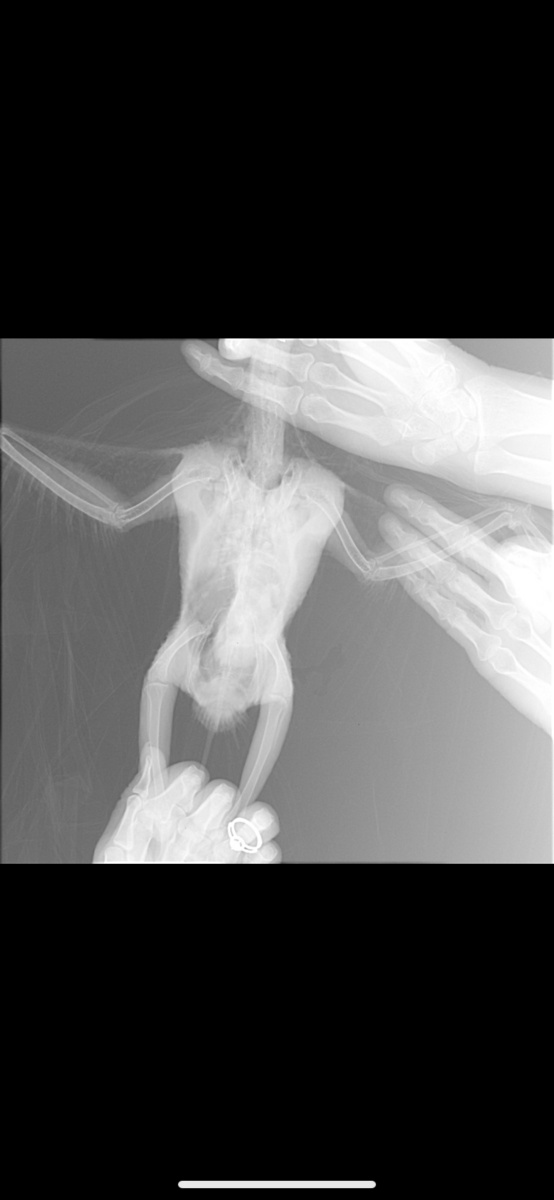

Koalla88 Опубликовано 26 февраля, 2020 #9 Опубликовано 26 февраля, 2020 @Жора жако гепатовет для кошек дают попугаям, это очень не плохой гепапротектор. Жако лечат вифендом, т.к. они этот препарат более-менее нормально переносят. Боятся выдержит ли птиц не стоит, тут два варианта - либо лечитесь и смотрите на динамику, либо просто наблюдайте, как птиц медленно умирает. Не будете лечить, птица однозначно погибнет. Поэтому пробуйте, в случае чего потом себя вам хотя бы будет не в чем упрекнуть.

Zosia Опубликовано 2 марта, 2020 #42 Опубликовано 2 марта, 2020 Обсудите с вашим врачом ингаляционное применение Энилконазола (торговые наименования и формы м.б. разные). Это- параллельно с вориконазолом. И нет ли у птицы "синдрома исчезающего легкого"... какой-то мне рентген привиделся...тревожный.

Жора жако Опубликовано 7 марта, 2020 Автор #43 Опубликовано 7 марта, 2020 03.03.2020 в 07:57, Zosia сказал: Обсудите с вашим врачом ингаляционное применение Энилконазола (торговые наименования и формы м.б. разные). Это- параллельно с вориконазолом. И нет ли у птицы "синдрома исчезающего легкого"... какой-то мне рентген привиделся...тревожный. Здравствуйте) Не увидели такого синдрома, симптомов никто из орнитологов не нашли Про энилконазол мне ответили, что Жако такого не назначают, так как не переносимость его???? Мы сдали биохимию и результаты не утешительны, к сожалению, особенно, что касается печени( боюсь, что может не выдержать лечение. @Zosia как специалист по Жако и по лечением травами, прошу вас посоветовать нашему птенцу ещё какую-нибудь поддержку, кроме гептрала ? (принимаем 1 таблетку в сутки, разделенную на 2 приема) Жорушка всё также не активный, сама его кормлю, так как не хочет есть (максимум подходит 1 раз к кормушке и 3-5 семечек может съесть), грудная клетка всё также увеличивается при дыхании, как на видео выше, практически не летает, ощипал себе шею, так как из-за постоянных кормлений, не всегда оперение супер чистое (стараюсь мыть после каждого кормления/дачи препаратов), контролируем анализ кала на наличие дрожжей, их нет. Из назначений: принимаем ворикоз , сумамед, гептрал, также с понедельника будут инъекции кальция внутримышечно ежедневно.